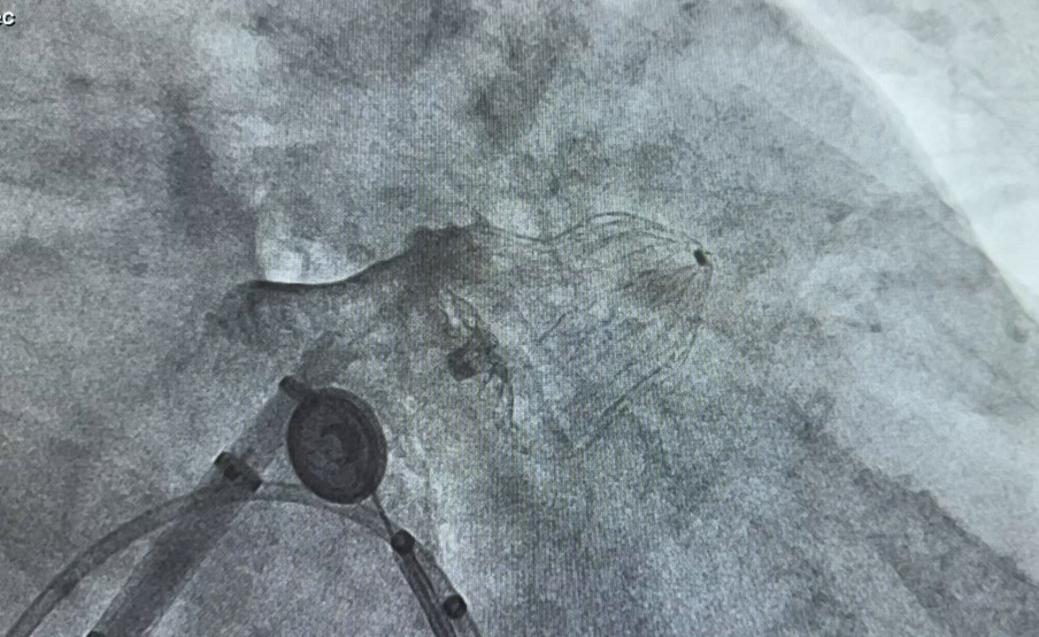

左心耳封堵器释放